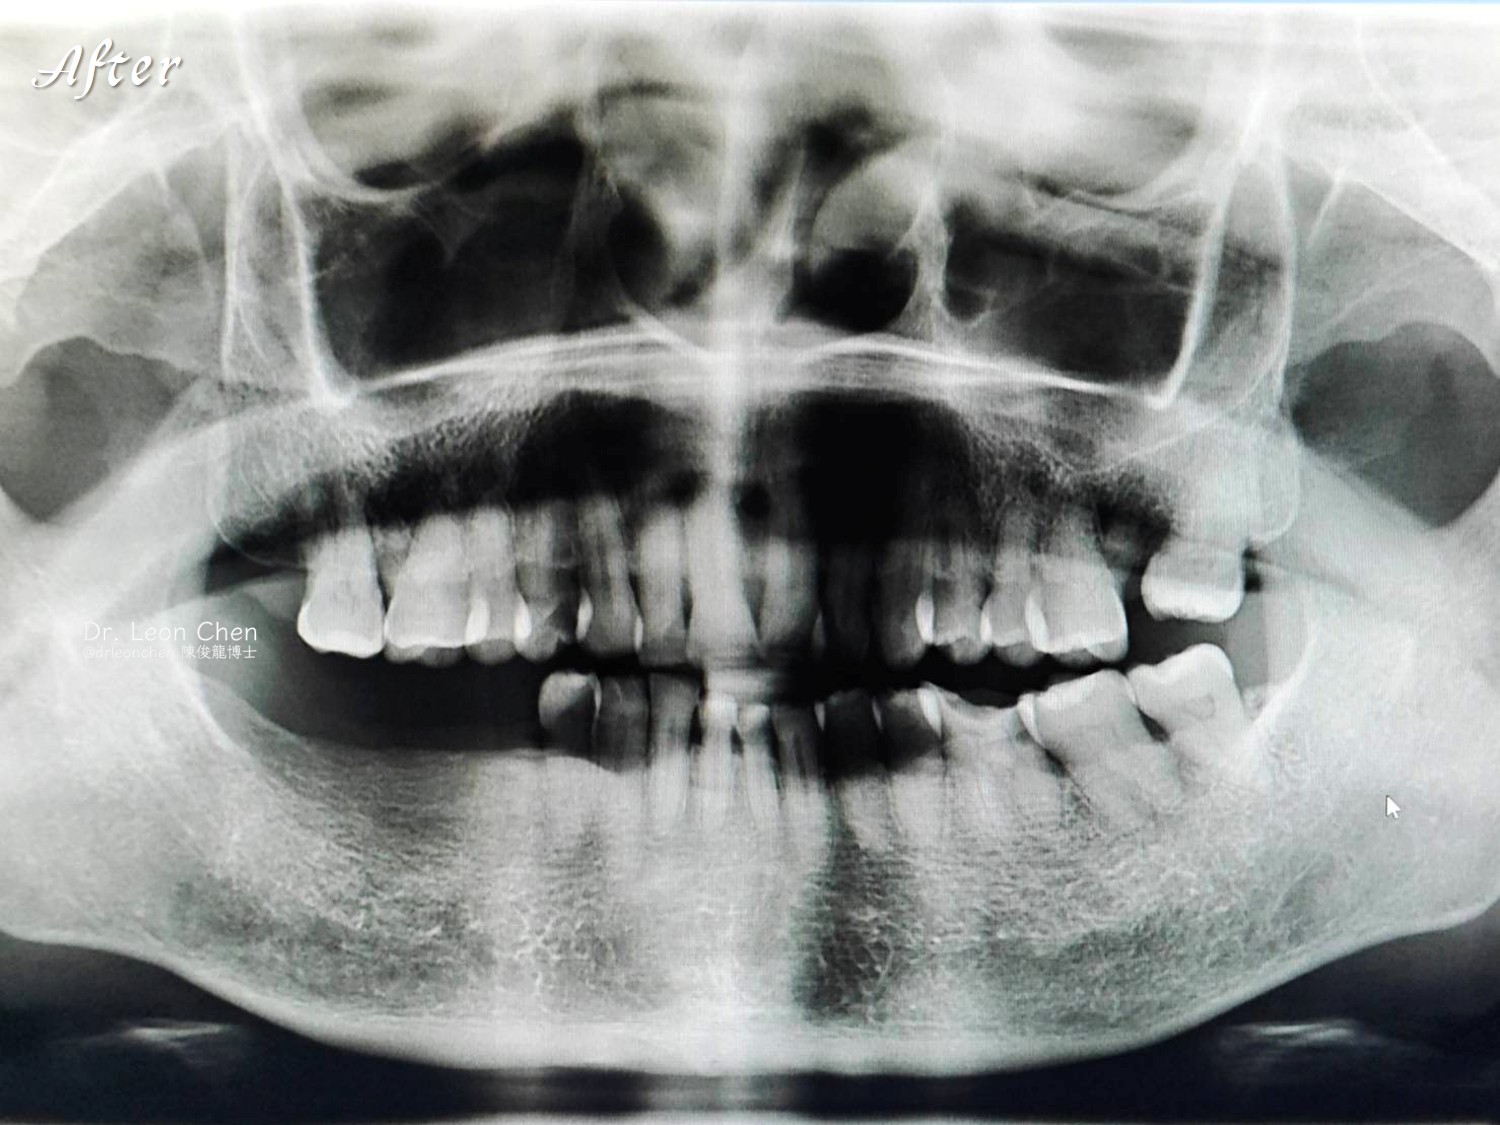

一位母親求醫無解:跨越兩年的全口重建故事

她最後飛往美國找到陳醫師,用三個小時一次全口重建,把所有複雜問題一次解決。

陳醫師解決了不但是生理上的痛苦,在大陸那裡,人口這麼多,理論上應該也有很多所謂的植牙名醫,卻都找不到醫師幫她植牙,終於來到台灣幸運遇上陳醫師,解決了這2年多的身心靈折磨,免於看精神科!